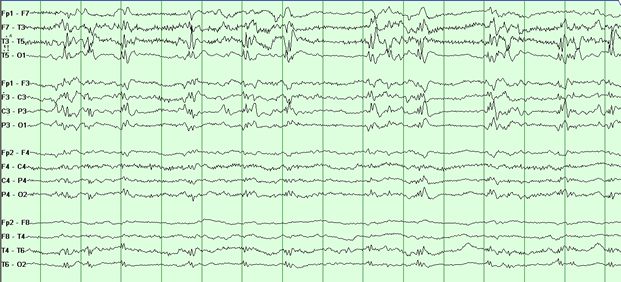

Rationale: Burst-suppression (BS) consists of periodic bursts of high-voltage slow waves and sharp waves in the electroencephalogram (EEG), alternating with attenuation of the background activity. Typical bihemispheric BS, whether pharmacologically-induced or secondary to encephalopathy, is often viewed as a non-epileptic phenomenon. On the other hand, unihemispheric BS is rare and its clinical significance is poorly understood. Methods: Two patients whose initial EEG tracings showed unihemispheric BS underwent continuous EEG monitoring in the intensive care unit. Patient-1 is a 56-year-old woman with a left temporoparietal tumor who presented in convulsive status epilepticus. Her EEG showed left hemispheric BS after clinical seizure termination with lorazepam and propofol. Patient-2 is a 39-year-old woman with multiple medical problems and a vague history of seizure disorder. After undergoing abdominal surgery, she experienced a convulsive seizure prompting treatment with propofol. Her EEG showed left hemispheric BS. Results: In both cases, titration of propofol resulted in disappearance of unihemispheric BS. The brain MRI of Patient-1 showed a mass lesion in the left anterior parietal area predominantly involving the white matter and the deep diencephalic structures with mass effect. The brain CT of Patient-2 showed left hemispheric encephalomalacia predominantly involving the left posterior parietal lobe. Both patients improved and were discharged from the hospital. Conclusions: The prevailing view that typical bihemispheric BS is a non-epileptic phenomenon should not be automatically extrapolated to unihemispheric BS. In the two cases presented, clinical seizures occurred and unihemispheric BS resolved easily with propofol, suggesting that an epileptic mechanism may be responsible for unihemispheric BS.